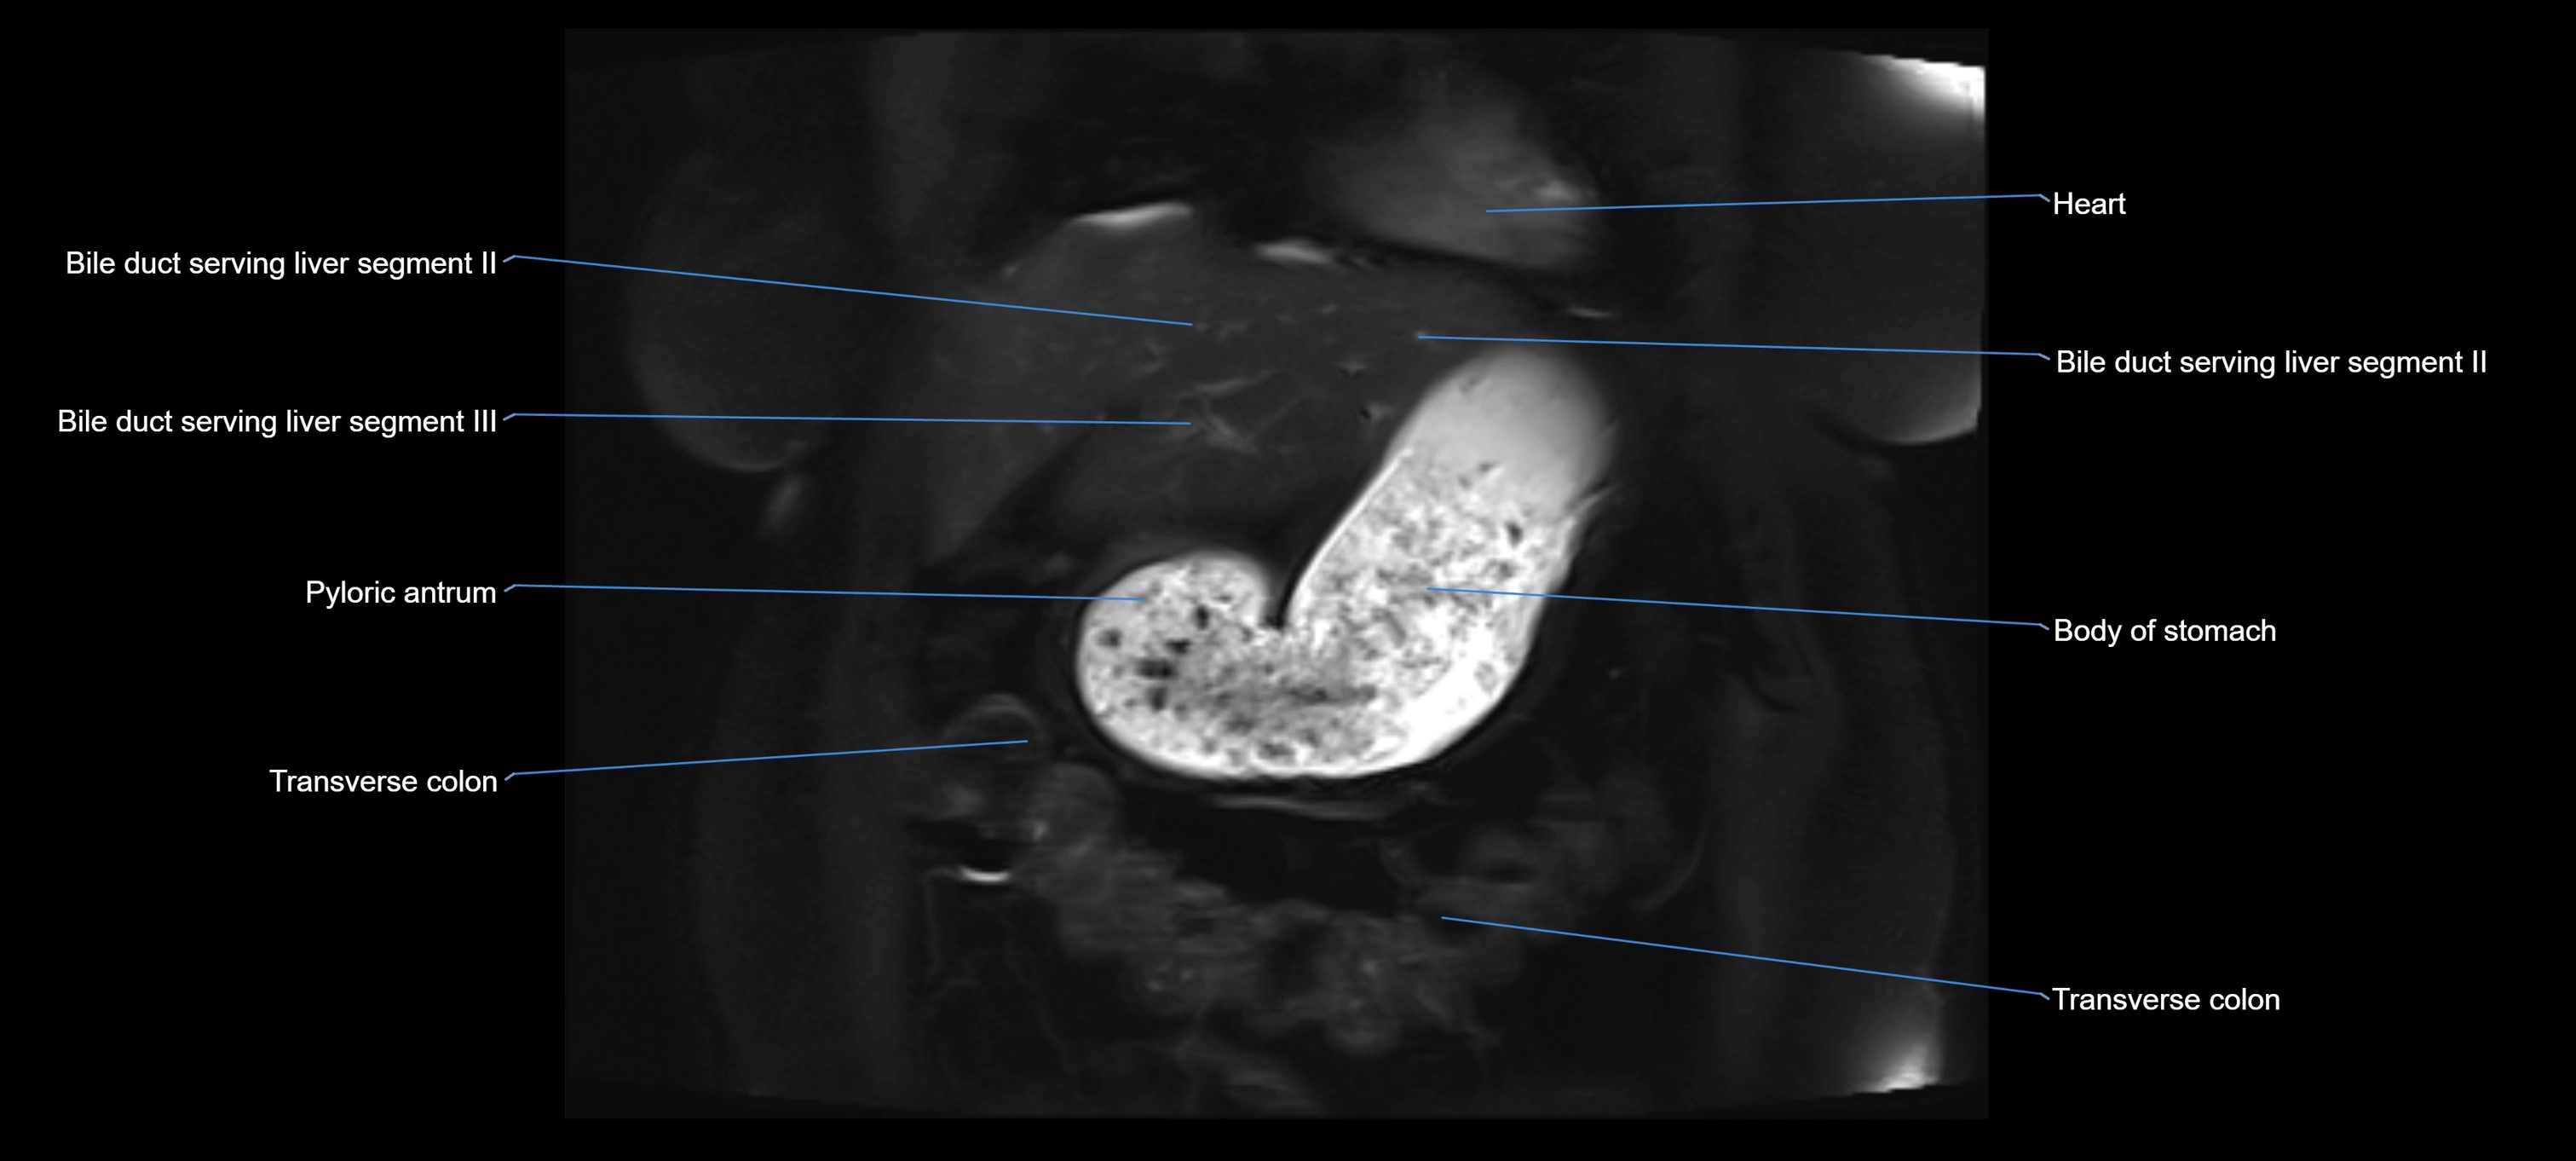

MRI image

image